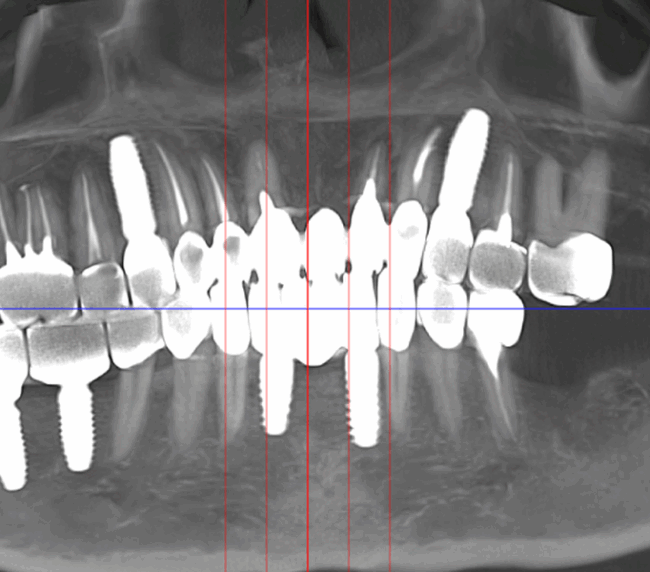

Tomografii (CBCT)

Caz 1

Caz 2

Reabilitarea complexă în stomatologie presupune refacerea completă a sistemului dentoalveolar, atât din punct de vedere funcțional, cât și estetic. Procesul începe cu o examinare detaliată a cavității bucale, interpretarea investigațiilor imagistice (CBCT), evaluarea musculaturii, articulațiilor temporomandibulare și a parametrilor estetici.

Tratamentul este coordonat de un medic responsabil, care gestionează întregul proces, implicând de regulă o echipă multidisciplinară formată din terapeut, ortodont, chirurg implantolog și protetist.